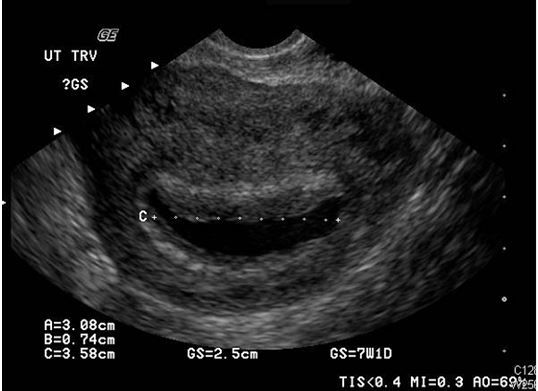

Results of a pelvic sonogram reveal the etiology of lower abdominal pain and vaginal bleeding in a 26-year-old woman.

Figure. Transvaginal sonogram.

A urine analysis and complete blood count (CBC) are performed with results that are normal but, perhaps not surprisingly, her pregnancy test comes back positive. A pelvic sonogram is completed by the ultrasound technologist. One of the transvaginal images is shown in the Figure.

The sonogram shows a sac in the uterus but this is not a normal gestational sac or a normal pregnancy. The presence of a pseudosac rather than a true gestational sac means that the pregnancy is likely elsewhere, or ectopic. Pseudosacs occur in about 10% of ectopic pregnancies and can lead the ultrasound technician, the radiologist, or the treating provider astray if they are identified as a sign of a normal pregnancy and not seen for what they truly are-a potential red herring.

As opposed to a normal gestational sac, a pseudosac is typically located centrally and may fill the entire endometrial cavity and it also lacks the “double ring” sign. True gestational sacs will usually be slightly off-center and will have a detectable double decidual sign. True sacs also will eventually develop an internal yolk sac later followed by an embryo, but pseudosacs will have neither.